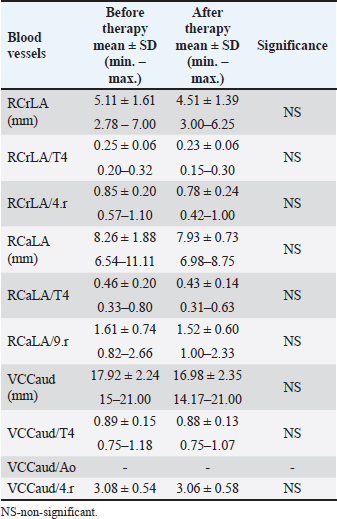

Dimensions of the RCrLA, the RCaLA, and the VCC were lower after therapy for HWD (Table 7). However, the dimensions of the blood vessels (RCrLA, RCaLA, VCC) in those eight dogs before and after therapy did not show a statistically significant difference, regardless of the form of width expressions (absolutely in mm or relatively as a ratio to different skeletal structures). The VCC/Ao ratio could only be measured in one dog before and after therapy, which made this parameter irrelevant for statistical analysis. Table 7. The blood vessel measurements before and after therapy in the dogs with HWD.

DiscussionThoracic radiography is a widely available diagnostic method used for the evaluation of cardiovascular and respiratory organ systems in small animal practice. In spite of its limitations, it is still used to assess the heart, blood vessels, and lung field. Interpreting dog radiographs can be challenging not only because of the wide variety of thoracic shapes and sizes in different breeds, but also due to positioning and technique. Furthermore, the numerous described radiographic methods for assessing heart size and shape [intercostal spaces, VHS, heart to single vertebra ratio (HSVR), MHS, SHS, TIHS, CSI, cardiothoracic ratio, tracheal-bifurcation angle, vertebral left atrial size, modified vertebral left atrial size, radiographic left atrial dimension, radiographic left atrial dimension to spine, bronchus to spine] seem to contribute to interpretation complexity. In the present study, radiographic methods relevant for the assessment of HWD characteristics were applied on radiographs of dogs with HWD in order to test their feasibility and determine their results. In clinical practice, diagnostic methods that are accurate, easy to perform, and no time consuming are the preferable ones. By comparing different methods on the same radiograph, it is possible to find out which diagnostic methods have higher potential over others in terms of feasibility. However, as this study shows, it is possible that in some patients more accurate and objective radiographic methods are inferior to others. Therefore, a holistic approach that includes both subjective and objective methods is required in interpreting dog radiographs. Subjective radiographic methods could be used in all dogs, while none of the applied objective methods could be used in two dogs, which had the most severe radiographic changes. Abnormal lung field, in the sense of massive opacities throughout several lung lobes, was the reason that prevented the assessment of the cardiac silhouette and blood vessels in these two dogs. Such changes raised suspicions about the existence of PTE, one of the most severe HWD complications. Subjective parameters of cardiomegaly, and even more so of abnormal lung patterns, could be assessed in the majority of dogs. However, the impossibility of assessing certain subjective parameters, even the most prevalent ones in the dogs with HWD, such as the size of the RCaLA in comparison to that of the corresponding vein, was observed. Pathological changes in the lung field, and incorrect positioning of the patient were mostly the reasons. Among the objective methods for the determination of cardiac size and shape, the most feasible ones were modified VHS, SHS, and CSI (in 38 out of 40 dogs for LL view, and 32 out of 36 dogs for DV view). The determination of cardiac size by MHS and TIHS was possible in only a smaller number of the dogs (in 23 and 26 dogs, respectively). While pathological lung changes prevented the determination of modified VHS, SHS, and CSI, particularly in DV radiographic view, the incorrect positioning of the dog and unsuccessful determination of the cranial M margin were the reasons for the impossibility of MHS and TIHS measurements. The assessment of the blood vessels relevant for HWD was most feasible for the RCrLA, followed by the VCC and the RCaLA, both for subjective and objective methods. In the case of the RCrLA, detection was possible in 36 dogs, both for the subjective method, in which it was compared with the corresponding vein, and for the objective methods, in which its width was expressed in mm, or as a ratio to the T4. It was possible to assess the VCC in comparison to the Ao, either subjectively or objectively, only in 17 dogs. However, it was more feasible to assess the VCC by direct measurement or indirectly as a ratio to the T4 (in 30 dogs) or to the 4.r (in 33 dogs). In the present study, objective methods of cardiac size and shape measurements were done as previously described (Guglielmini et al., 2012; Mostafa and Berry, 2017; Marbella Fernández et al., 2023a), with the exception of VHS, in which case the modified VHS was used. We have previously proved that no significant differences exist between heart size measured by the original VHS and the modified VHS methods in healthy dogs of the same breed (Spasojević Kosić et al., 2007), and in dogs with HWD of different breeds (Spasojević Kosić and Lalošević, 2025). Recently, the comparison of the cardiac axes with a single thoracic vertebra was also introduced as an objective method of evaluation of the cardiac silhouette (Costanza et al., 2022). The most accurate way of measurement in this, so-called, heart to single vertebra ratio (HSVR) is when the cardiac axes sum is compared with the length of the seventh thoracic vertebra (T7). Besides T7, other thoracic vertebrae can be used in the following order of preference T8, T5, T6, and, at the end T4, as it shows the lowest, although still acceptable level of agreement with VHS (Costanza et al, 2022). In our study, we used T4, not just because of the lack of significant difference from the original VHS method, but because of the uniformity of the measurements, since the blood vessels dimensions were also presented in this manner. We have found a very strong correlation between T4 and S4 (r=0.91, p < 0.05), and also significant but lower correlation between T4 and M (0.86, p < 0.05), and M and S4 (0.84, p < 0.05). However, there were no significant correlations between any of these skeletal structures and TI. This is opposite to the significant correlation found between TI and T4 in the study by Marbella Fernández et al. (2023a). In the study of Buchanan and Bücheler (1995), good correlations were detected between the LA dimension, SA dimension, and the sum of LA and SA dimensions and the 10 v reference length, as well as between heart size and the length of 3 or 4 sternebrae. Similarly, significant correlations were detected between cardiac LA, SA, the sum of the LA and SA, and the M length (Mostafa and Berry, 2017). These findings are in accordance with significant correlations, from very strong to moderate, detected in the present study between LA, SA, the sum of LA and SA, and each of the skeletal units (T4, S4, TI, M). In the study of Buchanan and Bücheler (1995), the M was excluded because of its variability, and the sternal measurements extended from the cranial edge of the second sternebra to the caudal edge of the fourth and fifth sternebrae were done. The purpose of the sternal measurement was to determine whether sternal length is more reliable than vertebral length as an index correlate for the heart size. As sternebral correlations were slightly less than vertebral correlations, no advantages of such measurement were seen, except in dogs with vertebral anomalies. In spite of these findings in dogs, and similar ones in cats (Litster and Buchanan, 2000; Ghadiri et al., 2008), sternebral heart score was not introduced as a method for heart size assessment until the recent study in ferrets (Gutiérrez et al., 2022). In accordance with the modified VHS method, the original SHS method (Gutiérrez et al., 2022) is modified in the present study, and a single sternebra, the S4 is used as a skeletal unit. In addition, a pronounced sternum arch in certain dogs due to chest conformation made it impossible to perform the measurement along the sternum. It was not difficult to perform this method, and it was equally feasible in the dogs with HWD as the modified VHS. Also, there were very strong and strong correlations between the S4 and the T4, and the S4 and heart size. Thus, the SHS method might be a useful method for evaluating heart size in dogs. However, the accuracy of each novel method of measurement should be estimated in comparison with gold standard methods, and its reproducibility should be tested so that an operator’s experience has a minimum impact on the results. Finally, reference values of measurement in healthy dogs should be defined. The subjective parameters of cardiomegaly, such as the increased sternal contact (91.89%), reversed “D” shape of the heart (89.65%), vascular patterns, such as the RCaLA enlargement (86.67%), and the loss of margination of pulmonary vessels (84.21%) were the most prevalent subjective radiographic parameters in the dogs with HWD. Similarly to our study, the reverse D shape of the heart, main pulmonary artery, and peripheral pulmonary artery dilation, as well as evidence of right heart failure were noted in the study by Kim et al. (2019). In another study (Maerz, 2020), enlarged peripheral pulmonary arteries were detected in the majority of dogs (65%), followed by parenchymal lesions (41%) and bulging of the main pulmonary artery (23.5%). In the study by Tudor et al. (2014), vascular radiographic changes (72.29%), pulmonary parenchymal changes (61.44%), and heart shape and silhouette changes (46.99%) dominated in the radiographs of dogs with HWD. Thrall and Calvert (1983) detected an enlarged right ventricle and RCaLA in every dog with HWD. These radiographic features were followed by pathological pulmonary abnormalities, enlarged RCrLA, main pulmonary artery, and VCC (Thrall and Calvert, 1983). Similar findings in dogs with HWD, such as the detection of right ventricular, main pulmonary, and RCrLA enlargement, were found by other authors (Losonsky et al., 1983). In the present study, pleural effusion was not detected in the dogs with HWD. The same result was reported in the study by Thrall and Calvert (1983), while Tudor et al. (2014) identified pleural effusions in 2.41% of dogs. Even though the parameters of cardiomegaly were more prevalent than the lung abnormality parameters, when radiographs before and after the HWD therapy were analyzed, no significant difference was found in the occurrence of the parameters of cardiomegaly, but among abnormal lung pattern parameters. After HWD therapy, the occurrence of main pulmonary artery enlargement in LL (p=0.0256; p ≤ 0.033, FDR), and the areas of increased opacity that tend to coalesce (p=0.0385; p ≤ 0.05, FDR) were significantly lower than before therapy. Thus, subjective radiographic assessment in the present study was able to register an improvement of lung pattern abnormalities, but not changes in cardiac size. In another study, radiographic features, such as increased pulmonary trunk, right atrial and ventricular enlargement, diffuse densification, and reticular interstitial lung patterning of the diaphragmatic lobes, became less frequent in the radiographs of the dogs after the therapy for HWD (Bendas et al., 2016). The only radiographic characteristic that was more frequent in dogs after the HWD therapy was increased diameter of the pulmonary arteries (Bendas et al., 2016). However, in the study of Bendas et al. (2016), the frequency of the radiographic features before and after the therapy, was expressed in absolute numbers without any statistical analysis. Cardiac size showed higher values in DV radiographs in all methods of objective measurement. In LL view, a heart size of 10.52 ± 0.97 v was measured by the modified VHS method, and in DV, the measured heart size was 10.79 ± 1.12 v. A similar value of VHS (10.59 ± 0.87 v in LL view) was measured in dogs of different breeds with HWD (Tudor et al., 2014). The value of VHS≤10.5 v is suggested as the clinically upper limit for normal heart size in most breeds (Buchanan and Bücheler, 1995). Despite the fact that thoracic radiography can underestimate the severity of HWD in small dogs, no significant difference was found between VHS in small and large breed dogs (Kim et al., 2019). Also, when values of VHS in LL and DV views were compared between dogs in different classes of HWD (classes 1–3), no significant difference was observed (Pajas and Acorda, 2018). When the M is used as a skeletal unit of cardiac size measurement, the mean value of 5.19 ± 1.80 was measured in LL radiographs in the present study. This value is similar to the value of MHS (5.2 ± 0.4) in large dogs with right-sided heart disease reported by other authors (Mostafa et al., 2020). More than overall MHS, the value of short MHS (the ratio of cardiac SA and the M length) is suggestive of right-sided heart disease (Mostafa et al., 2020). Known as a measure of cardiac shape, the CSI values of 0.86 ± 0.08 and 0.75 ± 0.07, in LL and DV views, respectively, were measured in the dogs with HWD in the present study. These values are lower than the CSI values of 88 ± 6.0 and 92 ± 8.0 measured in large and small dogs with right-sided heart disease (Mostafa et al., 2020), and in dogs with dirofilariasis belonging to various classes of HWD (Pajas and Acorda, 2018). By using TI as a skeletal unit, the heart size of 3.03 ± 0.41 was measured in LL radiographs of the dogs with HWD in the present study. This value is higher than the mean TIHS value of normal dogs (2.86 ± 0.27), but lower than the upper limit (3.2) of normal heart size in healthy dogs (Marbella Fernandez et al., 2023a). Although it is shown that a value of TIHS ≥ 3.3 can identify left heart enlargement in dogs with MMVD (Marbella Fernandez et al., 2023b), no studies on the subject of TIHS in right heart enlargement, right-sided heart disease, or HWD have been published yet. Values of 9.22 ± 1.04 and 9.49 ± 0.96 were measured by SHS in LL, and DV views, respectively. Since no values of SHS in healthy and diseased dogs have been published yet, it is not possible to compare this result with other studies. Similarly to the results of subjective radiographic assessment, no significant differences were detected between objective parameters of heart size and shape before and after therapy in the present study. However, another study shows that VHS has a tendency to increase after therapy for HWD in dogs with or without PH (Falcon Cordon et al., 2024b). In the study by Falcón Cordón et al. (2021), the RCrLA and the RCaLA expressed as a ratio to the ribs in dogs with HWD-induced PH were 1.4 ± 0.4 and 1.6 ± 0.6, respectively, while lower values (0.89 ± 0.25 for the RCrLA and 1.35 ± 0.40 for the RCaLA) were measured in the present study. There is a scarcity of reports about measurements of the pulmonary lobar arteries in HWD. On the other hand, several studies reported measurements of VCC. In dogs with dirofilariasis, classified in classes from 1 to 3, the VCC was measured as a ratio to Ao, T4, and 4.r (Pajas and Acorda, 2018). Our measurement of VCC/Ao (0.79 ± 0.20) was lower compared to the values in dogs in different classes of dirofilariasis (0.84 ± 0.11 – 1.02 ± 0.11) published by Pajas and Acorda (2018). The value of the VCC/T4 in our study (0.78 ± 0.15) was in the range of measured values in dogs in different stages of the disease (0.74 ± 0.07–0.81 ± 0.09) (Pajas and Acorda, 2018). However, the VCC/4.r in our study (2.58 ± 0.54) was higher than values reported in dogs in different classes of dirofilariasis (1.96 ± 0.21–2.25 ± 0.28) (Pajas and Acorda, 2018). Nonetheless, our measurements of the VCC (VCC/Ao, VCC/T4, VCC/4.r) were much lower than the values (VCC/Ao >1.50, VCC/T4 >1.30, VCC/4.r>3.50) reported for right sided heart abnormality by Lehmkuhl et al. (1997). Although observed, the diminishment of the relevant blood vessel diameters was not of statistical significance in the present study. The same findings for the lobar arteries were detected after HWD therapy in dogs without PH, but not in dogs with PH, where a significant increase in RCrLA/4.r and RCaLA/9.r ratios was observed after HWD therapy, indicating the persistence and worsening of the arterial damage (Falcon Cordon et al., 2024b). In this sense, it was concluded that RCrLA/4.r and RCaLA/9.r ratios, together with VHS, may be useful screening tools with which clinicians can decide whether to perform further diagnostic procedures, primarily echocardiography, to determine the presence of PH (Falcon Cordon et al., 2024a,b). Some limitations of the present study should also be addressed. The study design did not allow considerations of interobserver variability and interbreed variations for different radiographic methods. Due to the fact that SHS in normal healthy dogs has not been reported yet, it was not possible to compare the calculated value of SHS in the dogs with HWD. In addition, other diseases, mainly of cardiovascular and respiratory systems, which could influence or potentiate the radiographic features, were not ruled out by echocardiography. When HW infection is diagnosed, in order to establish the HWD diagnosis, both radiographic and echocardiographic examinations should be performed, as the two are considered complementary and successful in the classification of the disease and its risks. In addition, more sophisticated methods, like echocardiography and computed tomography, can definitely evaluate the utility and reliability of radiographic methods for HWD diagnosis. ConclusionOnly subjective radiographic assessment was possible in 5% of the dogs with HWD due to the severity of their lung abnormality pattern. Among the most prevalent parameters of cardiomegaly and abnormal lung patterns, increased sternal contact, reversed D cardiac shape, and loss of pulmonary vessel margination were available for the assessment in the highest number of dogs, while the RCaLA was possible to assess in the lowest number of dogs. The most feasible objective methods for the assessment of cardiac size and shape were the modified VHS, SHS, and CSI, while the most feasible ones for blood vessels were RCrLA/T4 and RCrLA/4.r. Heart sizes of 10.52 ± 0.97 and 10.79 ± 1.12 measured by the modified VHS method in LL and DV view, respectively, were slightly above the value for the normal dogs. In the present study, the values of the RCrLA in the dogs with HWD were 0.27 ± 0.08 for RCrLA/T4, and 0.89 ± 0.25 for RCrLA/4.r. Finally, the present study revealed subjective parameters as superior to objective parameters in defining an improvement in the radiographs after therapy. Conflict of interest The author declares that there is no conflict of interest. Funding This work was partly supported by the Ministry of Science, Technological Development and Innovation, Republic of Serbia (contract number 451-03-137/2025-03/200117). Author’s contributions Lj. Spasojević Kosić performed all measurements and analyses, wrote the manuscript and created all tables and figures. Data availability All data supporting the findings of this study are available within the manuscript. ReferencesAckerman, N. 1987. Radiographic aspects of heartworm disease. Semin. Vet. Med. Surg. 2, 15–27. AHS. 2025. American heartworm society canine guidelines for the prevention, diagnosis, and management of heartworm (Dirofilaria immitis) infection in dogs. Available via https://d3ft8sckhnqim2.cloudfront.net/images/AHS_Canine_Guidelines_WEB_19JUN2025.pdf? Arya, M., Tyagi, S.P., Kumar, A., Kumar, A. and Kumar, S. 2021. Radiographic mensuration of Caudal Vena Cava, Aorta, vertebral length and fourth rib width and ascertaining their ratios in healthy dogs. Indian J. Anim. Res. B-4676, 1–4. Atkins, C.E., Keene, B.W. and Mcguirk, S.M. 1988. Pathophysiologic mechanism of cardiac dysfunction in experimentally induced heartworm caval syndrome in dogs: an echocardiographic study. Am. J. Vet. Res. 49, 403–410. Azevedo, G.M., Pessoa, G.T., Moura, L.D.S., Sousa, F.D.C.A., Rodrigues, R.P.D.S., Sanches, M.P., Fontenele, R.D., Barbosa, M.A.P.D.S., Neves, W.C., Sousa, J.M.D. and Alves, F.R. 2016. Comparative study of the Vertebral Heart Scale (VHS) and the cardiothoracic ratio (CTR) in healthy poodle breed dogs. Acta. Sci. Vet. 44, 1387. Bavegems, V., Van Caelenberg, A., Duchateau, L., Sys, S.U., Van Bree, H. and De Rick, A. 2005. Vertebral heart size ranges specific for Whippets. Vet. Radiol. Ultrasound 46, 400–403. Bendas, A., Rodrigues, A.C.M., Soares, D.D.V., Labarthe, N.V. and Mendes-de-Almeida, F. Radiographic findings of Dirofilaria immitis in naturally infected dogs submitted to slow-kill adulticide treatment. In Proceedings of the 2016 WSAVA Congress, 2016. Available via https://www.vin.com/members/cms/project/defaultadv1.aspx?pId=19840&catId=105918&id=8250044&ind=165&objTypeID=17 Benjamini, Y. and Hochberg, Y. 1995. Controlling the false discovery rate: a practical and powerful approach to multiple testing. J. R. Stat. Soc. B Method. 57(1), 289–300. Buchanan, J.W. 1968. Radiology of the heart. In Proceedings of the 35th Annual Meeting of the American Animal Hospital Association 1968, American Animal Hospital Association, South Bend, Indiana, pp 34–45. Buchanan, J. 2000. Vertebral scale system to measure heart size in radiographs. Vet. Clin. North. Am. Small. Anim. Prac. 30(2), 379–393. Buchanan, J.W. and Bücheler, J. 1995. Vertebral scale system to measure canine heart size in radiographs. J. Am. Vet. Med. Assoc. 206, 194–199. Calvert, C.A. and Losonsky, J.M. 1985. Pneumonitis associated with occult heartworm disease in dogs. J. Am. Vet. Med. Assoc. 186, 10, 1097–1098. Calvert, C.A., Losonsky, J.M., Brown, J., and Lewis, R.E. 1986. Comparisons of radiographic and electrocardiographic abnormalities in canine heartworm disease. Vet. Radiol. 27, 2–7. Castro, M.G., Tôrres, R.C.S., Araújo, R.B., Muzzi, R.A.L. and Silva, E.F. 2011. Radiographic evalu-ation of the cardiac silhouette in clinically normal Yorkshire Terrier dogs through the vertebral heart size method. Arq. Bras. Med. Vet. Zootec. 63, 850–857. Costanza, D., Greco, A., Piantedosi, D., Bruzzese, D., Pasolini, M.P., Coluccia, P., Castiello, E., Baptista, C.S. and Meomartino, L. 2022. The heart to single vertebra ratio: a new objective method for radiographic assessment of cardiac silhouette size in dogs. Vet. Radiol. Ultrasound 64(3), 378–384. Dunn, J.K. 2000. Diseases of the cardiovascular system. In Textbook of small animal medicine. Ed., Dunn, J.K. London, UK: WB Saunders, pp: 255–344. Empel, W. 1974. Beurteilung der Grosse und Gestalt des Herzschattens des Deutschen Schäferhundes. Kleintierprax 19, 7–13. Falcón Cordón, S., Carretón Gómez, E., Rivero, J.I.M., Costa Rodríguez, N., Rodríguez, S.N.G. and Alonso, J.A.M. Utility of thoracic radiology as clinical indicator of pulmonary hypertension in dogs with heartworm disease (Dirofilaria immitis). In Proceedings of the 28th International Conference of the World Association for the Advancement of Veterinary Parasitology, 2021. Available via https://www.researchgate.net/publication/353435749_Utility_of_thoracic_radiology_as_clinical_indicator_of_pulmonary_hypertension_in_dogs_with_heartworm_disease_Dirofilaria_immitis Falcón-Cordón, S., Falcón-Cordón, Y., Caro-Vadillo, A., Costa-Rodríguez, N., Montoya-Alonso, J.A. and Carretón, E. 2024b. Association between thoracic radiographic changes and indicators of pulmonary hypertension in dogs with heartworm disease. Animals 14(13), 1900; doi:10.3390/ani14131900 Falcón-Cordón, S., Falcón-Cordón, Y., Costa-Rodríguez, N., Matos, J.I., Montoya-Alonso, J.A. and Carretón, E. 2024a. Assessment of thoracic radiographic alterations in dogs with heartworm and their correlation with pulmonary hypertension, pre- and post-adulticide treatment. Animals 14, 2551; doi:10.3390/ani14172551 Ghadiri, A., Avizel, A., Resekh, A. and Yadegari, A. 2008. Radiographic measurement of vertebral heart size in healthy stray cats. J. Feline Med. Surg. 10, 61–65. Guglielmini, C., Diana, A., Santarelli, G., Torbidone, A., Di Tommaso, M., Baron Toaldo, M. and Cipone, M. 2012. Accuracy of radiographic vertebral heart score and sphericity index in the detection of pericardial effusion in dogs. J. Am. Vet. Med. Assoc. 241, 1048–1055. Gulanber, E.G., Gonenci, R., Kaya, U., Aksoy, O. and Biricik, H.S. 2005. Vertebral scale system to measure heart size in thoracic radiographs of Turkish Shepherd (Kangal) dogs. Turk. J. Vet. Anim. Sci. 29, 723–726. Gutiérrez, A., Ezquerra, L.J., Rodríguez, P.L. and Jiménez, J. 2022. Cardiac radiographic measurements in ferrets using the OsiriX MD programme. Front. Vet. Sci. 8, 795947; doi:10.3389/fvets.2021.795947 Hansson, K., Haggstrom, J., Kvart, C. and Lord, P. 2005. Interobserver variability of vertebral heart size measurement in dogs with normal and enlarged hearts. Vet. Radiol. Ultrasound 46, 122–130. Harvey, C.E. and Fink, E.A. 1982. Tracheal diameter: analysis of radiographic measurements in brachycephalic and nonbrachycephalic dogs. J. Am. Anim. Hosp. Assoc. 18, 570–576. Herrtage, M. and Denis, R. 1997. The thorax. In Manual of small animal diagnostic imaging, 2nd ed. Ed., Lee, R. Quedgeley, UK: BSAVA, pp: 43–67. Jepsen-Grant, K., Pollard, R.E. and Johnson, L.R. 2013. Vertebral heart scores in eight dog breeds. Vet. Radiol. Ultrasound. 54, 3–8. Jones , S.L. 2016. Canine caval syndrome series part 2: a practical approach to diagnosing caval syndrome. TVP. 2016, 63–67. Kealy, J.K. 1979. Diagnostic radiology of the dog and cat. Philadelphia, PA: WB Saunders. Keith, J.C., Schaub, R.G. and Ralings, C. 1983. Early arterial injury induces myointimal proliferation in canine pulmonary artery. Am. J. Vet. Res. 44, 181–186. Kim, S.Y., Park, H.Y., Lee, J.Y., Lee, Y.W. and Choi, H.J. 2019. Comparison of radiographic and echocardiographic features between small and large dogs with heartworm disease. J. Vet. Clin. 36(4), 207–211. Kitoh, K., Katoh, H., Kitagawa, H., Nagase, M., Sasaki, N. and Sasaki, Y. 2001. Role of histamine in heartworm extract-induced shock in dogs. Am. J. Vet. Res. 62(5), 770–774. Kitoh, K., Watoh, K., Chaya, K., Kitagawa, H. and Sasaki, Y. 1994b. Clinical, hematological, and biochemical findings in dogs after induction of shock by injection of heartworm extract. Am. J. Vet. Res. 55, 1535–1541. Kitoh, K., Watoh, K., Kitagawa, H. and Sasaki, Y. 1994a. Blood coagulopathy in dogs with shock induced by injection of heartworm extract. Am. J. Vet. Res. 55(11), 1542–1547. Kittleson, M.D. 1998. Heartworm infestation and disease (Dirofilariasis). In Small animal cardiovascular disease. Eds., Kittleson, M.D. and Kienle, R.D. Mosby, St. Louis, MI, pp: 370–401. Knight, D.H. 1980. Evolution of pulmonary artery disease in canine dirofilariasis: evaluation by blood pressure measurements and angiography. In the Proceedings of the 1980 Heartworm Symposium, Veterinary Medicine Publishing Co, Edwardsville, Kansas, pp: 55–62. Lamb, C.R., Tyler, M., Boswood, A., Skelly, B.J. and Cain, M. 2000. Assessment of the value of the vertebral heart scale in the radiographic diagnosis of cardiac disease in dogs. Vet. Rec. 146, 687–690. Lamb, C.R., Wikeley, H., Boswood, A. and Pfeiffer, D.U. 2001. Use of breed specific ranges for the vertebral heart scale as an aid to the radiographic diagnosis in dogs. Vet. Rec. 148, 707–711. Lehmkuhl, L.B., Bonagura, J.D., Biller, D.S. and Hartman, W.M. 1997. Radiographic evaluation of caudal vena cava size in dogs. Vet. Radiol. Ultrasound. 38(2), 94–100. Litster, A. and Buchanan, J. 2000. Vertebral scale system to measure heart size in radiographs of cats. J. Am. Vet. Med. Assoc. 216, 210–214. Lombard, C.W. and Ackerman, N. 1984. Right heart enlargement in heartworm-infected dogs: a radiohraphic, electrocardiographic, and echocardiographic correlation. Vet. Radiol. 25(5), 210–217. Losonsky, J.M., Thrall, D.E. and Lewis, R.E. 1983. Thoracic radiographic abnormalities in 200 dogs with spontaneous heartworm infestation. Vet. Radiol. 24(3), 120–123. Maerz, I. 2020. Clinical and diagnostic imaging findings in 37 rescued dogs with heartworm disease in Germany. Vet. Parasitol. 283, 109156; doi:10.1016/jvetpar.2020.109156 Marbella Fernández, D., García, V., Santana, A.J. and Montoya-Alonso, J.A. 2023a. The Thoracic inlet heart size, a new approach to radiographic cardiac measurement. Animals 13, 389; doi:10.3390/ani13030389 Marbella Fernández, D., García, V., Santana, A.J. and Montoya-Alonso, J.A. 2023b. The thoracic inlet length as a reference point to radiographically assess cardiac enlargement in dogs with myxomatous mitral valve disease. Animals 13, 2666; doi:10.3390/ani13162666 Marin, L.M., Brown, J., Mcbrien, C., Baumwart, R., Samii, V.F. and Couto, C.G. 2007. Vertebral heart size in retired racing greyhounds. Vet. Radiol. Ultrasound. 48, 332–334. Mostafa, A.A. and Berry, C.R. 2017. Radiographic assessment of the cardiac silhouette in clinically normal large- and small-breed dogs. Am. J. Vet. Res. 78(2), 168–177. Mostafa, A.A. and Berry, C.R. 2022. Radiographic vertical tracheal diameter assessment at different levels along the trachea as an alternative method for the evaluation of the tracheal diameter in non-brachycephalic small breed dogs. BMC. Vet. Res. 18, 61; doi:10.1186/s12917-022-03160-4 Mostafa, A.A., Peper, K.E. and Berry, C.R. 2020. Use of cardiac sphericity index and manubrium heart scores to assess radiographic cardiac silhouettes in large-and small-breed dogs with and without cardiac disease. J. Am. Vet. Med. Assoc. 256(8), 888–898. Olive, J., Javard, R., Specchi, S., Belanger, M., -C.., Belanger, C., Beauchamp, G. and Alexander, K. 2015. Effect of cardiac and respiratory cycles on vertebral heart score measured on fluoroscopic images of healthy dogs. J. Am. Vet. Med. Assoc. 246, 1091–1097. Owens, J.M. 1985. Radiology of the heart. In Manual of small animal cardiology, Eds. Tilley, L.P. and J.M. Owens. New York, NY: Churchill Livingstone, pp: 25–54. Pajas, A.M.G. and Acorda, J.A. 2018. Echocardiographic, electrocardiographic and thoracic radiographic findings in dogs with dirofilarioasis. Philipp. J. Vet. Med. 55(2), 71–84. Polizopoulou, Z.S., Koutinas, A.F., Saridomichelakis, M.N., Patsikas, M.N., Desiris, A.K., Roubies, N.A. and Leontidis, L.S. 2000. Clinical and laboratory observations in 91 dogs infected with Dirofilaria immitis in northern Greece. Vet. Rec. 146(16), 466–469. Rawlings, C.A., Keith, J.C., Lewis, R.E., Losonsky, J.M., McCall, J.W. 1983. Aspirin and prednisolone modification of radiographic changes caused by adulticide treatment in dogs with heartworm disease. J. Am. Vet. Med. Assoc. 182, 131–136. Schaub, R.G., Rawlings, C.A. and Keith, J.C. 1981. Platelet adhesion and intimal proliferation in canine pulmonary arteries. Am. J. Pathol. 104, 13–22. So, J., Chung, J., Je, M., Kang, K., Choi, J. and Yoon, J. 2024. Development and feasibility of new cardiac measurement method using vertebral heart area ratio in dogs. J. Vet. Med. Sci. 86(1), 28–34. Spasojević Kosić, Lj, Krstić, N., Trailović, D.D. 2007. Comparison of three methods of measuring vertebral heart size in German shepherd dogs. Acta Vet. 57(2-3), 133–141. Spasojević Kosić, Lj, Lalošević, L., Kozoderović, G., Vračar, V., Simin, S. and Potkonjak, A. 2024. Effectiveness of doxycycline/ivermectin therapy for heartworm disease in regard to Wolbachia status in dogs. J. Helenic. Vet. Med. Soc. 75(1), 7173–7180. Spasojević Kosić, Lj, and Lalošević, V. 2025. Radiographic diagnostic of the canine heartworm disease: old and new methods. In Proceedings of the 8th ESDA Days and 2025 Annual EVPC Scientific meeting, European Society of Dirofilariosis and Angiostrongylosis (ESDA), European Veterinary Parasitology College (EVPC), Thessaloniki, Greece, p 77. Spasojević Kosić, Lj, Lalošević, V., Naglić, A., Simin, S., Lj, K. and Spasović, A. 2016. Subjective and objective assessment of radiographic findings in dogs with heartworm disease. Parasit. Vectors 10(Suppl 1), 5. Suter, P.F. and Lord, P.F. 1984. Cardiac diseases. a text atlas of thoracic diseases of the dog and cat. Wettswil, Switzerland. Thrall, D.E. and Calvert, C.A. 1983. Radiographic evaluation of canine heartworm disease coexisting with right heart failure. Vet. Radiol. 24(3), 124–126. Torad, F.A. and Hassan, E.A. 2014. Two-dimensional cardiothoracic ratio for evaluation of cardiac size in German Shepherd Dogs. J. Vet. Cardiol. 16, 237–244. Tudor, N., Ionita, L., Tapaloaga, D., Tudor, P., Ionita, C. and Vlagioiu, C. 2014. Radiographic cardiopulmonary changes in dogs with heartworm disease. Rom. Biotechnol. Lett. 19(6), 9918–9924. Ware, W. 2011. Heartworm disease. In Cardiovascular disease in small animal disease. Ed., Ware, W London, Uk: Manson Publishing/The Veterinary Press, pp: 351–71. | ||